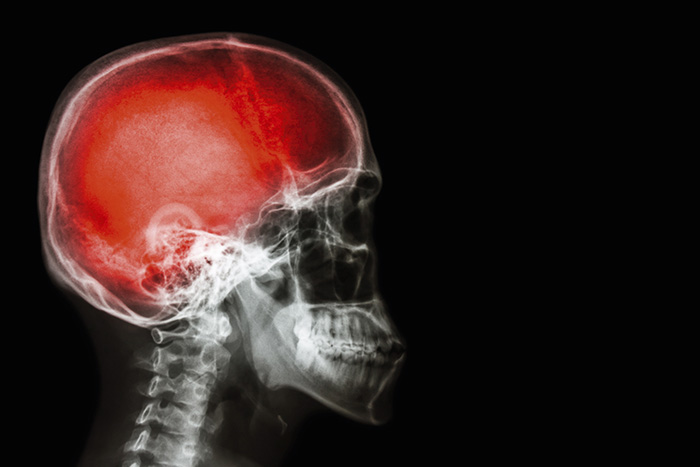

Traumatisk hjärnskada ökar risken för demens

Patienter som drabbats av en traumatisk hjärnskada löper ökad risk att drabbas av demens. Det visar en amerikansk studie som presenteras i tidskriften JAMA Neurology.

För individer under 55 års ålder var måttlig till svår hjärnskada kopplad till ökad risk att drabbas av demens, och för patienter över 65 även måttliga hjärnskador.